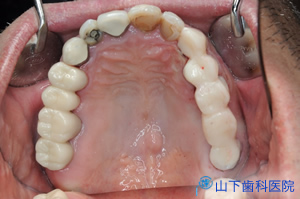

| 治療前 | 治療後 |

| 「入れ歯」では思うように噛めず、気持ち悪い。前歯で噛んでいるがぐらぐらしてきた。 残る歯もすっきりしない所が多々あり、今後に不安を抱えて来院されました。 |

| 上下の奥歯が咬み合うことで決まる咬合が不安定で、下の前歯が上の前歯を突き上げています。 予知性がない右下、左上の4番目を抜歯して落ち着いた状態です。 |

| 咬み合せの状態がよく、左右均等に何でも噛めて、不安なくなり、体調もよくなったとご満足頂いています。 | ![]() ![]() |